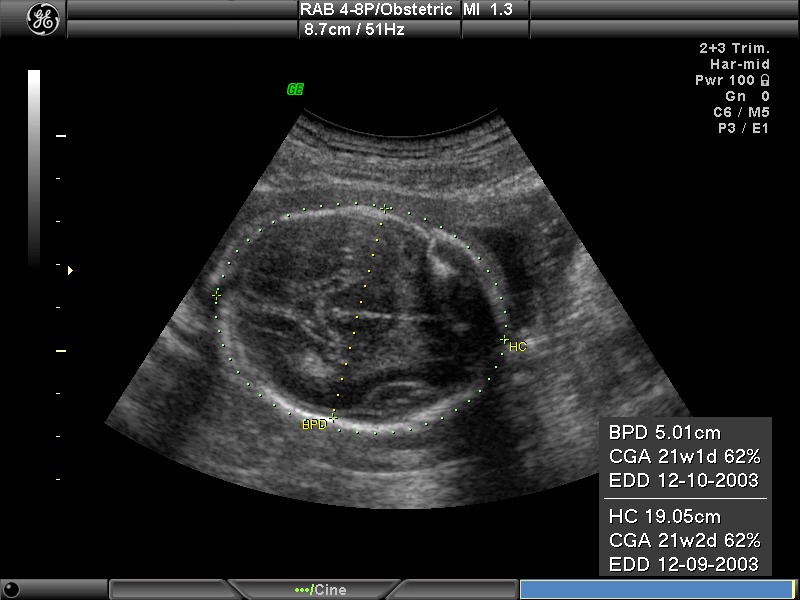

- Đánh giá sự phát triển của thai nhi: So sánh FL với các chỉ số như BPD (đường kính lưỡng đỉnh), HC (chu vi đầu), AC (chu vi bụng) để kiểm tra sự phát triển cân đối của thai nhi.

Chỉ số FL (Femur Length) được đo bằng cách xác định chiều dài xương đùi của thai nhi qua hình ảnh siêu âm. Đây là xương dài nhất trong cơ thể thai nhi và dễ nhận biết khi thai đã phát triển đủ. Việc đo FL thường được thực hiện từ khoảng tuần thai thứ 12 trở đi, khi xương đùi đã hiển thị rõ ràng trên màn hình siêu âm.